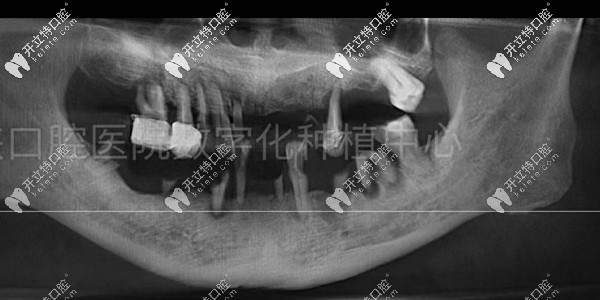

種牙前的口腔檢查